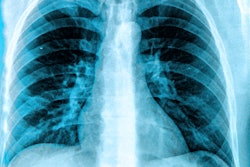

Be sure to take a look at our coverage of Prof. Dr. Christiane Kuhl, PhD's remarks to the German news magazine Der Spiegel regarding the state of breast cancer screening in Europe, and of research that suggests that the deep-learning algorithm Mirai shows promise for detecting interval breast cancers.